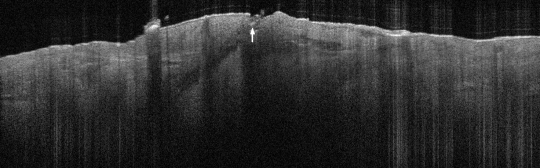

VA34: Right Temple, Actinic Keratosis, Hypotrophic, Focally reaching the base.

- White arrow denotes hair follicle

VA34: Right Temple, Adjacent, Normal

- Note normal hair follicle presentation